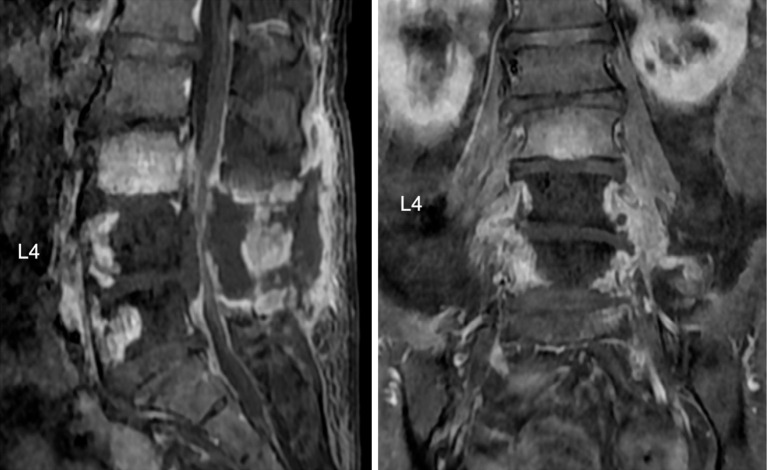

Abstract Image